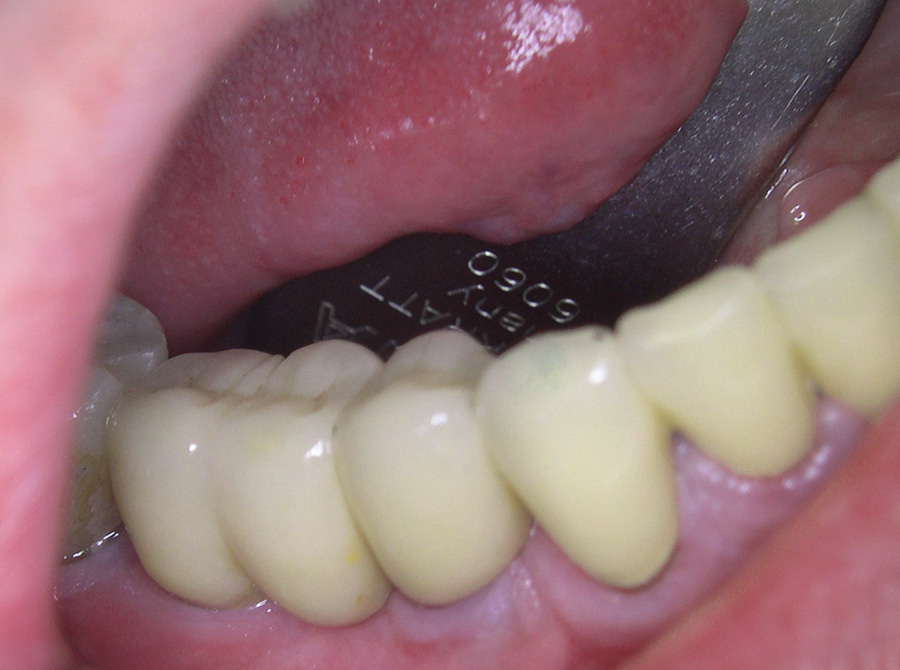

Ein besonderer positiver Effekt der Implantate ist, dass sie den Kieferknochen und das Zahnfleisch erhalten, während sich der Knochen unter Brücken und Prothesen hingegen abbaut. In vielen Fällen lässt sich so die natürliche Rot-Weiß-Ästhetik, also das harmonische Zusammenspiel von Zahnfleisch und Zähnen erhalten, so dass implantat-getragene Kronen kaum von eigenen gesunden Zähnen zu unterscheiden sind.